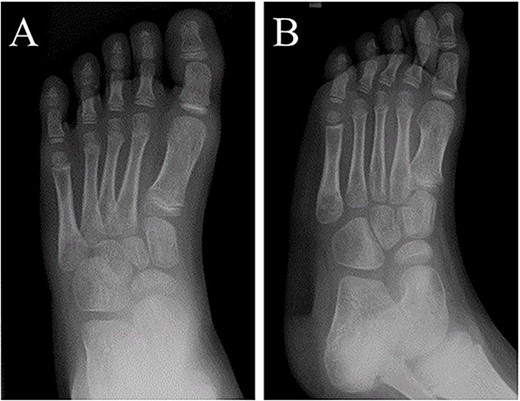

A 21-month-old Japanese female infant presented with a swollen mass on the dorsolateral aspect of the left foot. Her parents noticed the mass and brought the patient to our hospital. The patient had no past medical histories or complications prior to the occurrence. In addition, she received the BCG vaccine at the age of 4 months in Japan. At first visit to our hospital, physical examination revealed the ~3 × 3 cm mass was located on the dorsolateral aspect of the left foot and was hard accompanied by local heat (Fig. 1). Plain radiographs of the left foot showed a lytic lesion without periosteal reaction in the fifth metatarsal bone (Fig. 2). Magnetic resonance imaging (MRI) showed an isointense lesion on T1-weighted images and a hyperintense lesion on T2-weighted images around and within fifth metatarsal (Fig. 3). Gallium scintigraphy revealed intense uptake in the patient’s left foot (Fig. 4). In addition, laboratory examination was within normal. Based on medical history, clinical and imaging findings, we considered the possibility of neoplasia or osteomyelitis and performed an open debridement and biopsy of the lesion to make a diagnosis. The lesion was yellow and consisted of weak, adipose-like tissue that surrounded and continued into the inferior of the fifth metatarsal bone (Fig. 5). The lesion inside and outside the bone was resected as much as possible. Histopathologic examination of the lesion showed granulomatous inflammation including anaplastic giant cells, Langerhans-type giant cells and caseous necrosis (Fig. 6). Based on these results, TB or BCG osteomyelitis was considered as a diagnosis. The tuberculin test was positive, but the QuantiFERON TB test was negative. In addition, samples analyzed using polymerase chain reaction did not identify M. tuberculosis, but did identify the BCG Tokyo-172 strain. Per these findings, the patient was diagnosed with BCG osteomyelitis of the fifth metatarsal and oral treatment with anti-TB medicine including isoniazid (100 mg/day) and rifampicin (150 mg/day) was started. Clinical findings included reduction in swelling of the mass and gradual remodeling of the lytic lesion of the fifth metatarsal on plain radiographs (Fig. 7). However, 10 months after starting the anti-TB treatment, the mass recurred, and MRI revealed a residual high-intensity lesion around and inside the fifth metatarsal on T2-weighted fat-suppressed images (Fig. 8). It was determined that the lesion was difficult to control with anti-TB treatment alone, so an open debridement for the lesion was performed again. Histopathologic examination of the lesion revealed an epithelioid granuloma with necrosis. Therefore, the anti-TB treatment was continued. Six months after the second surgery, clinical and radiographic image findings showed complete improvement (Fig. 9). As a result, anti-TB treatment was ended. At the time of writing this report, 8 years after starting anti-TB treatment, there has been no recurrence.

Plain radiographs of the left foot showing a lytic lesion without periosteal reaction in the fifth metatarsal bone in (A) anteroposterior and (B) oblique views.